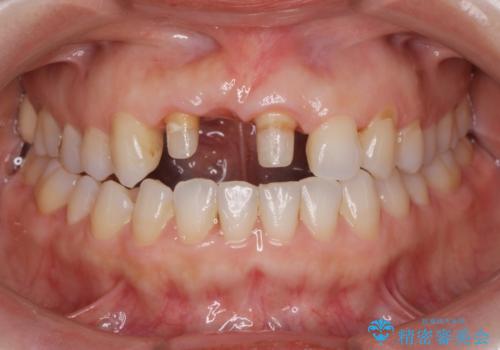

- 前歯のブリッジがすぐに外れる、歯ぐきが腫れている、見た目を良くしたい、と希望され来院されました。

現在装着されているブリッジを除去したところ、歯ぐきよりも上に存在する歯質(縁上歯質)が少なく、土台の形態の悪さや不適合などさまざまな問題があります。

根管治療を行ったのち、歯周外科を行うことで、欠損部の歯ぐきの厚みを出し、縁上歯質を獲得することで、長期的な予後の見込めるブリッジを製作できる環境を整備していきます。